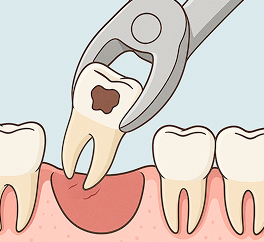

歯のほとんどが失われ、根だけが残っている状態で、神経もすでに死んでおり痛みを感じないです。 抜歯を検討することが一般的ですが、状態によっては歯を残せる可能性もあります。

出血を止めるために、10~15分程度ガーゼを噛んでください。

傷口をふさぐかさぶた(血餅)が取れてしまい、治りが遅くなります。

やけどや舌や頬の内側を噛んでしまうことを防ぎます。

血流が良くなり、血が止まりにくくなることがあります。